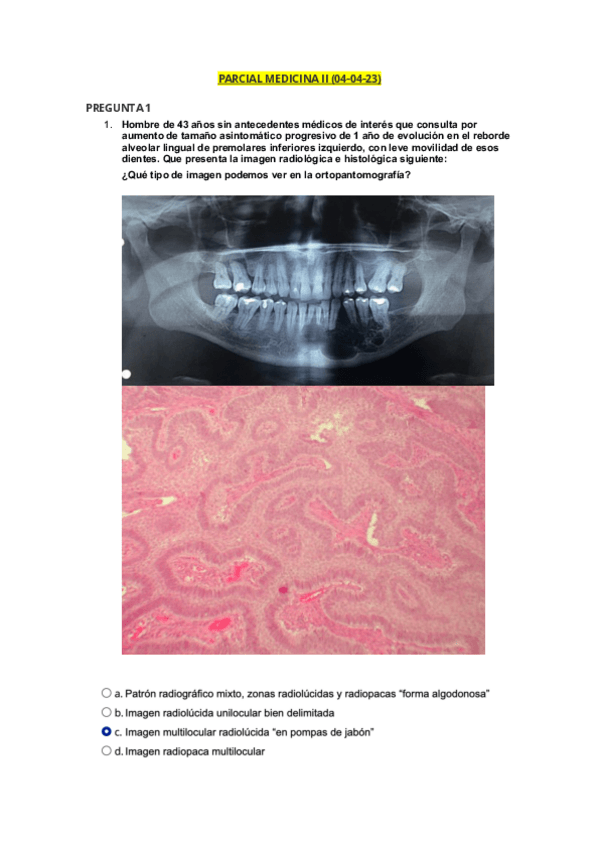

He publicado nuevos examenes de 3º Medicina Bucal II: PARCIAL-MEDICINA-II.pdf

5 páginas